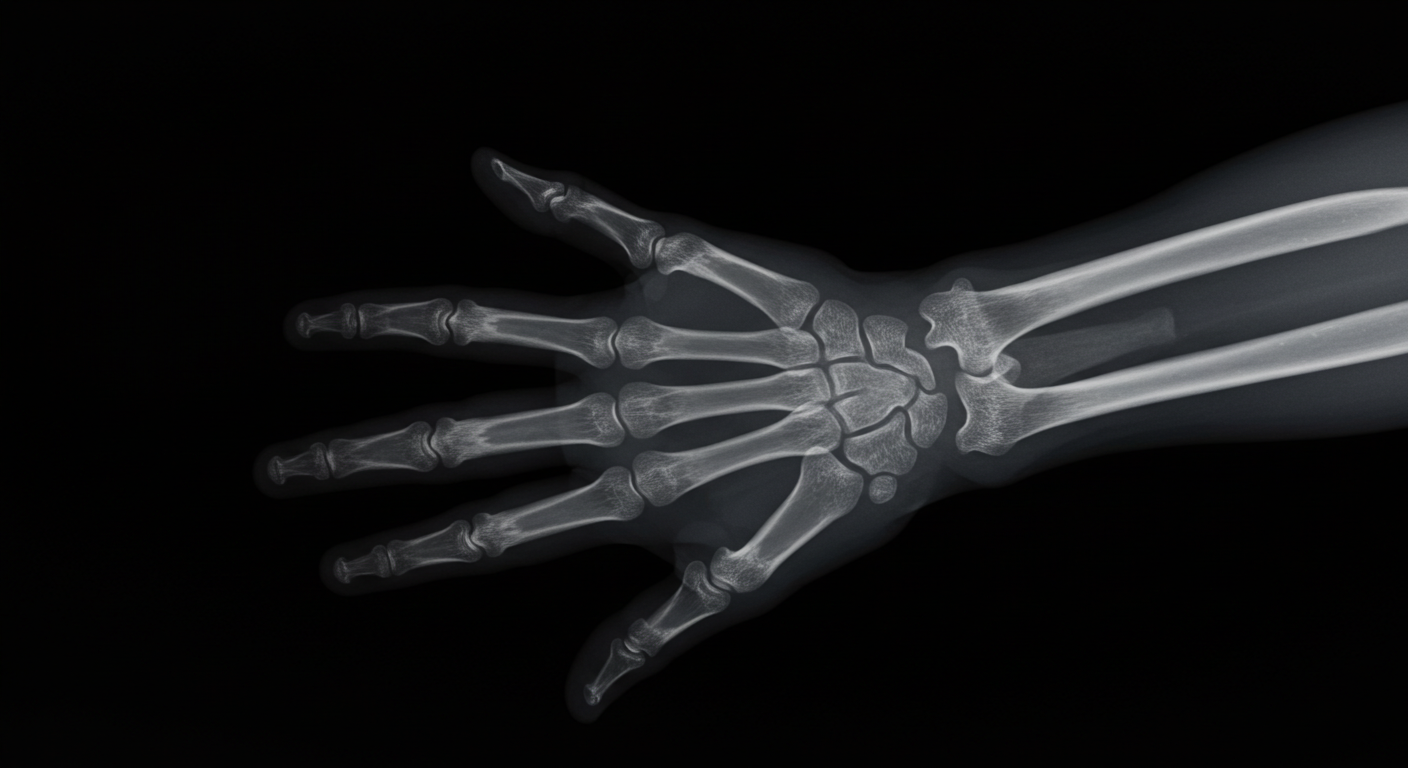

レントゲンはこの「正体不明」の光線を、数学で未知を表す記号にちなんで「X線」と名付けます。そして数週間後、妻アンナ・ベルタの手を撮影した世界初のX線写真を見て、彼女は叫びました——「私は自分の死を見た!」

しかし、妻の手の骨が写った写真は、疑いようのない証拠でした。1895年12月28日、レントゲンは論文「On a New Kind of Rays(新種の光線について)」を発表します。1896年1月1日、彼は90通の封筒を郵便局から発送しました。論文の抜き刷りと、そのうち12通には、妻の手を含む9枚のX線写真が同封されていました。

わずか3ヶ月後の1896年2月3日。アメリカ・ダートマス大学で、医療史を変える出来事が起きます。天文学教授エドウィン・フロストと医師の兄ギルマン・フロストが、アイススケートで転倒し手首を骨折した少年、エディ・マッカーシーのX線撮影に成功しました。これが、アメリカで最初の臨床X線使用です。